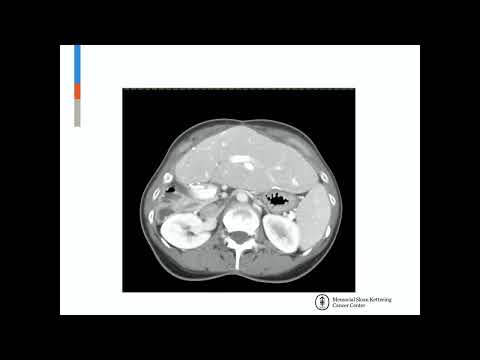

DEB09: HCC Macrovascular Invasion Resection

Debate 09: HCC Macrovascular Invasion Resection

KN08: Liver Resection in Advanced HCC

Keynote Lecture 08: Liver Resection in Advanced HCC